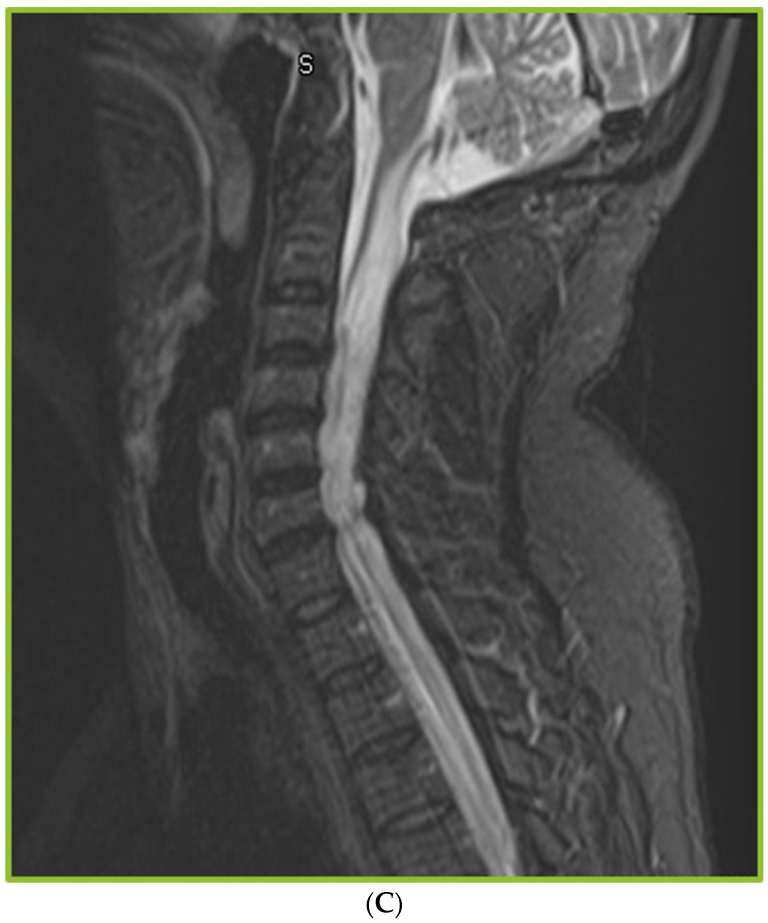

背景:球孢子菌性脑膜炎(CM)是最具侵袭性的球孢子菌病,需要终生抗真菌治疗,通常需要脑脊液(CSF)转移。长期CM可与脊髓并发症如蛛网膜炎相关。然而,描述CM患者蛛网膜炎的频率、临床和影像学特征的研究有限。方法:2010年1月至2020年12月,我们通过脑脊液培养、PCR或血清学鉴定了133例CM患者。其中,37例患者接受了脊柱成像。回顾了人口统计学、危险因素、症状、抗真菌治疗、手术治疗、随访、依从性、血清学趋势和影像学结果等方面的数据。结果:37例CM患者行脊柱影像学检查,其中30例出现异常。在我们的研究中,影像学异常包括轻脑膜增强(53%)、蛛网膜炎(53%)、脊髓空洞(23%)、脊髓信号异常(10%)和骨髓炎(7%)。在这30名患者中,90%的人有虚弱、麻木或尿潴留等症状。本研究中蛛网膜炎的发生率为12%。较高的初始脑脊液蛋白水平和颅内压与发生蛛网膜炎/脊髓空洞的高风险相关。CM的管理是具有挑战性的,分流失败(46%),药物不依从性(57%)和缺乏足够的随访(60%)。62%的患者存在持续性残疾。结论:CM患者可出现蛛网膜炎或脊髓空洞等脊柱并发症。由于在早期阶段缺乏症状,许多病例可能未被发现。CM管理的挑战,如分流失败,缺乏随访护理,药物不依从,是常见的。

Background: Coccidioidomycosis meningitis (CM) is the most aggressive form of coccidioidomycosis, requiring lifelong antifungal treatment and often cerebrospinal fluid (CSF) diversion. Long-standing CM can be associated with spinal complications such as arachnoiditis. However, studies describing the frequency, clinical, and imaging characteristics of arachnoiditis in patients with CM are limited. Methods: We identified 133 patients with CM based on CSF culture, PCR, or serology between January 2010 and December 2020. Of these, 37 patients underwent spinal imaging. Data on demographics, risk factors, symptoms, antifungal therapy, surgical management, follow-up visits, adherence, serological trends, and imaging findings were reviewed. Results: Abnormal findings were observed in 30 of the 37 patients with CM who underwent spinal imaging. The imaging abnormalities noted in our study included leptomeningeal enhancement (53%), arachnoiditis (53%), syringomyelia (23%), cord signal abnormalities (10%), and osteomyelitis (7%). Of the 30 patients, 90% had symptoms, such as weakness, numbness, or urinary retention. The incidence of arachnoiditis in the present study was 12%. Higher initial CSF protein levels and intra cranial pressure were associated with a higher risk of developing arachnoiditis/syringomyelia. Management of CM was challenging, as evidenced by shunt failure (46%), medication non-compliance (57%), and lack of adequate follow-up (60%). Persistent disabilities were noted in 62% of the patients. Conclusions: Patients with CM develop spinal complications such as arachnoiditis, or syringomyelia. Many cases may go undetected due to lack of symptoms in early stages. CM management challenges such as shunt failure, lack of follow-up care, and medication noncompliance, were frequent.